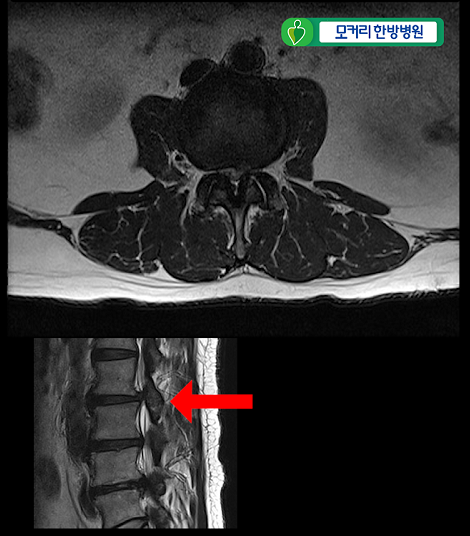

<2-3번>

이 환자분은 협착증을 25년간 앓으시고 증상도 매우 심하신 환자분입니다.

허리 세 마디 2번 3번, 3번 4번, 4번 5번, 이렇게 세 마디의 척추관이 심하게 막혀 있습니다.